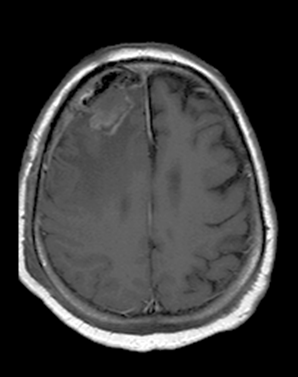

Image

15. Glioblastoma multiforme in the right frontal lobe, MRI (T1W+contrast).